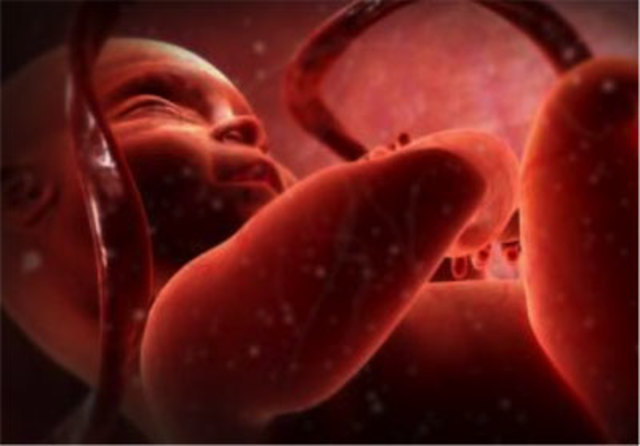

El embrión a formado todos los órganos. Las extremidades ya están formadas. El embrión se mueve y disfruta de todo su espacio dentro del saco amniótico.

Mide 5,5 cm y pesa 9 g. Poco a poco, su cabeza está más erguida y va tomando forma redondeada.

Los ojos, cubiertos por unos finísimos párpados, se van situando en la parte delantera de la cara y sus orejas avanzan hacia su ubicación definitiva.

Las fosas nasales están todavía bastante separadas.

Las cuerdas vocales hacen su aparición.